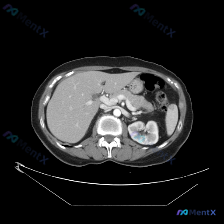

这是一张腹部CT增强扫描横断面图像,视野内所见:

- 脾脏:大小、形态正常,边缘光滑;实质密度均匀,增强后血管显影良好,未见明确占位、囊变、出血或异常强化灶。

- 其他腹部脏器(肝、胰、部分胆道、左肾、肾上腺):均未见明确异常密度或占位;腹膜后未见肿大淋巴结;腹主动脉、下腔静脉走行自然;腹腔内未见游离气体、积液或梗阻征象。

- 总体印象:这张单帧图像上,未发现需要紧急处理的“红旗征象”,也未发现明确的病理性异常。